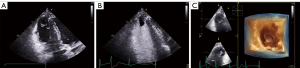

Electrocardiogram showed inverted T-waves and the Epsilon waves in leads V1–V3 (Figure 2). In view of the impaired cardiac function, we performed an echocardiogram (echo), which revealed a dilated right atrium (RA) at 59 mm × 65 mm, an expanded right ventricle (RV) at 31 mm × 37 mm with dysfunction (Figure 3A), the right ventricle outflow tract (RVOT) in parasternal short-axis view at 38 mm (Figure 3B), severe tricuspid regurgitation covering an area of 11.4 cm2, tricuspid annular plane systolic excursion (TAPSE) 13 mm and left ventricular ejection fraction (LVEF) 56% (Figure 3C). There was a pedicled mass about 26 mm × 16 mm in the apex of the RV (Figure 4A). Contrast echocardiography of the right heart was performed to define the nature of the mass, which showed that the microbubbles were not filled with the mass (Figure 4B). We also used real-time echocardiographic 3-dimensional (3D) imaging to observe the morphology of the mass (Figure 4C). Given the positive D-dimer and RA and RV dilation, we further examined the coagulation indices, arterial oxygen saturation, and lower-limb compression (through ultrasonography) to preliminarily rule out acute pulmonary embolism (PE). All the tests were negative. According to the recommendations of the European Society of Cardiology (ESC) Task Force for the diagnosis and management of acute PE (5), we considered that the patient had no predisposing factors for PE, and rather that they fulfilled the exclusion criteria for it. Based on these findings, we suspected that he was experiencing ARVC with right ventricular thrombosis, as he met 4 major criteria out of the 2010 revised Task Force criteria. The 4 major criteria for diagnosis are as follows: (I) severe dilation and dyskinesia of RV; (II) inverted T waves in leads V1–V3; (III) Epsilon wave in leads V1–V3; (IV) unsustained ventricular tachycardia of left bundle-branch morphology (6). To confirm the diagnosis, the patient underwent cardiac magnetic resonance (CMR) imaging. It was revealed that the left atrium and left ventricle were normal in morphology and function, but the RA and RV were significantly enlarged with dyskinesia. The RA was enlarged to 56 mm, the RV was enlarged to 47 mm, and the right ventricular wall was significantly thinner. The RV ejection fraction was 10%, the RV end-systolic volume was 187 mL, end-diastolic volume was 208 mL, and stroke output was 21 mL. The RV end-diastolic volume index (RVEDVI) was 115.7 mL/m2. The RV apex showed “shallow lobulated” changes with unclear demarcation from subepicardial fat, and diffuse strip-shaped abnormal enhancement shadows were observed under the endocardial wall of the right ventricular wall after delayed scanning, which was thought to be due to replacement of myocardial tissue by fibrous adipose tissue. After enhanced scanning, irregular low-signal filling defects were observed in the right ventricular apex, which was considered a sign of thrombosis. The above phenomena increased our certainty that the patient had ARVC with thrombosis (Figure 5). Since ARVC is rarely associated with thrombosis, we were interested to further study genetic relationship of this thrombosis. Unfortunately, the patient refused undergo the relevant genetic testing. We then gave the patient oral rivaroxaban 15 mg once a day as empiric anticoagulation to further confirm thrombus formation and prevent a embolic complications. Furthermore, we kept the patient on sotalol to control his arrhythmias and improve his outcome. An echo obtained 10 days later showed that the thrombus had significantly reduced to a size of 11 mm × 6 mm. This helped us to more clearly identify the presence of a thrombus, and that rivaroxaban had had a good treatment effect. Repeat echocardiography after about 4 weeks of sufficient anticoagulation indicated complete disappearance of the RV thrombus (Figure 6). Afterwards, an ICD was installed as secondary prevention of SCD.